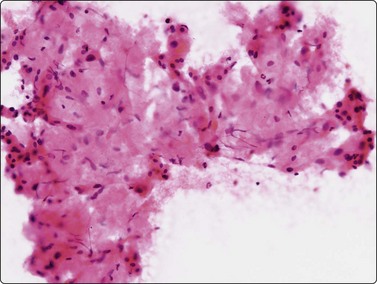

Cholangiocarcinoma

Intrahepatic cholangiocarcinoma (CC) is associated with etiological factors such as liver fluke infestation (common in parts of South-east Asia), the primary sclerosing cholangitis/ulcerative colitis complex, congenital conditions such as Caroli’s disease and intrahepatic lithiasis. Tumors typically occur at the hilum where they present early with obstructive jaundice. They may be difficult to diagnose although the use of EUS-FNA has reported good results.66,171

Criteria for diagnosis (Fig. 10.27)172

Sheets, clusters and microglandular arrangement showing nuclear crowding and overlapping,

Decreased cell cohesion,

Small to medium cuboidal/columnar cells resembling bile duct epithelium,

Variable nuclear enlargement and pleomorphism,

Prominent nucleoli in the less well-differentiated tumors,

Delicate cytoplasm with fine vacuolization, positive for mucin,

Occasionally fragments of stroma.

Cholangiocarcinomas often have abundant, desmoplastic stroma and may prove difficult to sample by FNA, or CNB for that matter. Although cells from a well-differentiated cholangiocarcinoma may not appear too different from bile duct epithelium, hepatocytes are absent and the number and size of epithelial sheets are larger than are usually obtained from non-neoplastic liver tissue (Fig. 10.27A). The application of P53, bcl-2 and Ki-67 has been reported as useful in discriminating between them.173 Less well-differentiated carcinomas are indistinguishable from metastatic adenocarcinoma (Fig. 10.27B), particularly those of pancreatic origin. Unfortunately, they are both generally positive for CK7 and CK19 and negative for CK20.174 Distinction from HCC relies on adenocarcinoma showing positivity for mucin and diffuse cytoplasmic staining for CK7, CK19 and pCEA and HCC staining for alpha fetoprotein and HepPar-1 and others as described earlier in the section on HCC.

Diagnosis depends not only on cytological assessment but on correlation of the clinical and radiological findings, in particularly excluding an extrahepatic malignancy.